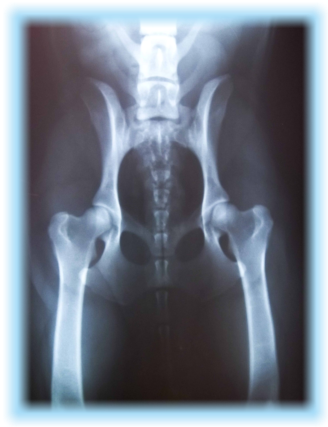

H

D A

ED - frei

OCD frei

Interpretation: Der untersichte Hund ist reinerbig

für das intakte Gen.